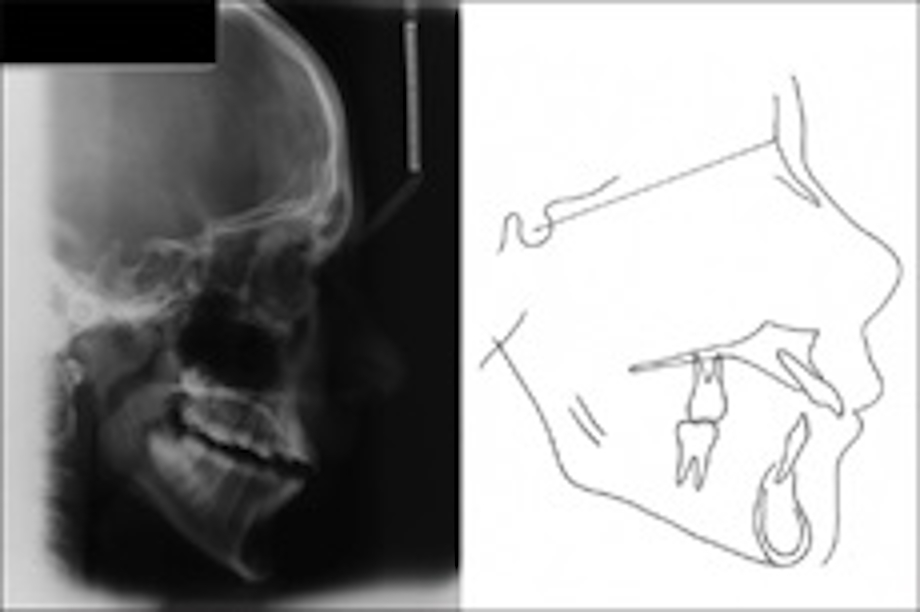

Figure 3: Pretreatment cephalometric radiograph and its tracing

Pretreatment cephalometric radiograph and its tracing